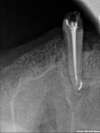

2 mois plus tard, le kyste a quasi disparu et nous avons pu obturer la dent

Puis la nouvelle couronne est remise et l'appareil réadapté.